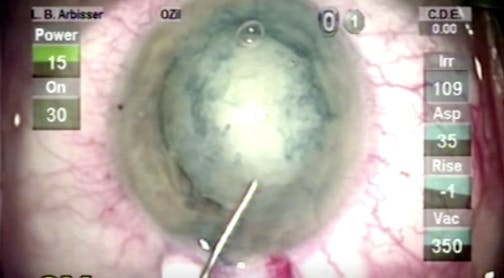

Intumescent Cataract

Lisa Brothers Arbisser, MD